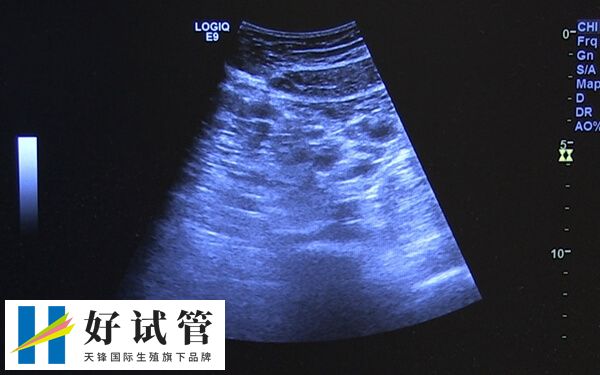

试管临床上,长方案促排卵泡治疗周期应用的比较多,不过因个体之间存在较大的差异,所以部分患者在使用长方案促排卵之后,可能会出现卵泡大小不一样的情况,而这也可能是以下几点导致的。

长方案促排卵泡大小不匀称可能由多种因素导致,比如说患者如果存在卵巢功能减退,那么由于雌激素和孕激素的异常,通常会导致FSH提前升高,这就会使卵泡发育不均,进而出现有些卵泡过于成熟,而有效卵泡则为小卵泡等情况。

如果患者长方案促排卵泡大小不一样,也可能是卵泡本身存在发育异常,可能会影响卵泡的健康发育,进而导致有些卵泡可能发育不够成熟,而有些则可能已经成熟的情况。